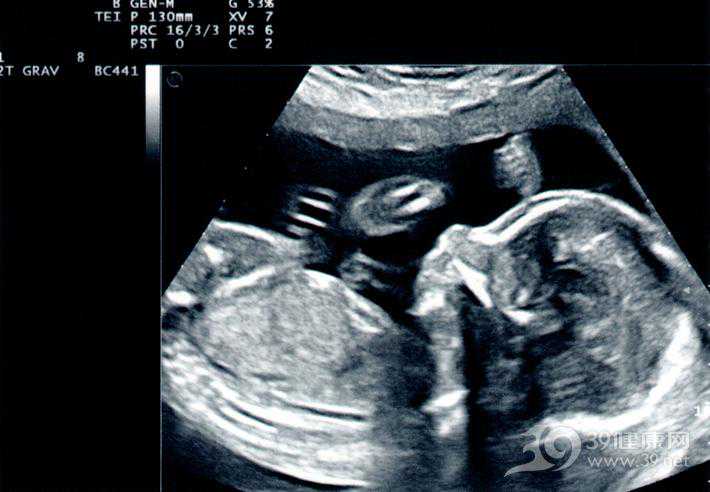

待情绪稳定下来,小刘跟丈夫就询问医生,当时说怀的是三胞胎,怎么又变成四胞呢?医生解释说,产检大多数时候是准确的,但也有例外。尤其是怀多胞胎的时候,胎儿的手脚都搭在一起,B超只显示一个正面图,很难看清。